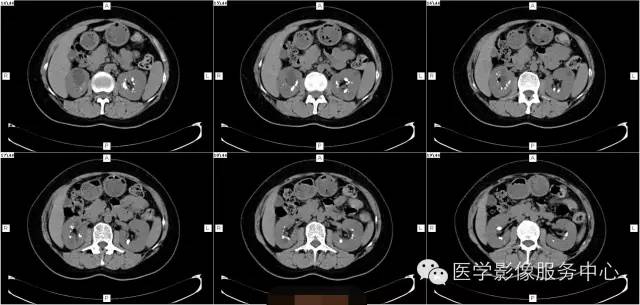

病史:

女,37岁,血尿一周

髓质海绵肾(简称MSK)又称Cacchi Ricci disease,是一种先天发育性肾髓质囊性病变,发生率约1:2000-5000,多见于40-60岁男年,70%为双侧肾脏发病,病变局限于髓质范围内,常累及两侧肾的多数锥体和乳头,形成许多数毫米的囊腔使髓质如海绵状,故名海绵肾,病理特点为集合管远端扩张,形成圆形或不规则型囊腔,囊内壁衬以立方或扁平上皮,囊内充溢脱离的上皮及钙化形成的小结石。

临床表现:

1、多数患者无症状,实验室检查正常。

2、若并发感染、结石可出现血尿,绞疼,尿路刺激征。

1、腹部平片表现肾影正常或稍增大,两侧或单侧肾实质内多发圆形、类圆形或不规则形结石,直径2-5MM,呈簇状或扇形分布,有时平片可表现阴性。

2、静脉肾盂造影表现肾脏大小正常或轻度增大,造影剂在肾乳头或扩张集合管呈放射条纹状、花束状,肾功能一般正常。

3、CT平扫表现一个或多个肾锥体内散在或蔟团状多发结石,呈花瓣样或扇形分布;部分腹部平片阴性,CT平扫可发现肾锥体内细小的结石。增强扫描表现扩张的肾集合管内有条纹状、刷状、小囊状或扇形的造影剂浓聚。部分患者肾实质内可见多发小囊肿。